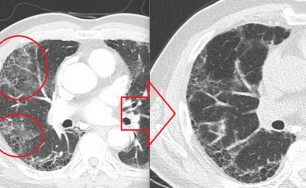

이러한 면역체계의 과민 반응이 기관지에 생기면 기관지벽이 두꺼워지고 그로 인해서 직경이 좁아지게 됩니다.

즉 천식은 기도 통로가 좁아지면 공기가 원활하게 지나가지 못하므로 호흡이 어려워져서 기침, 천식음(쌕쌕 거리는 소리), 호흡곤란, 가슴답답 등이 반복적으로 발생하는 질환입니다.